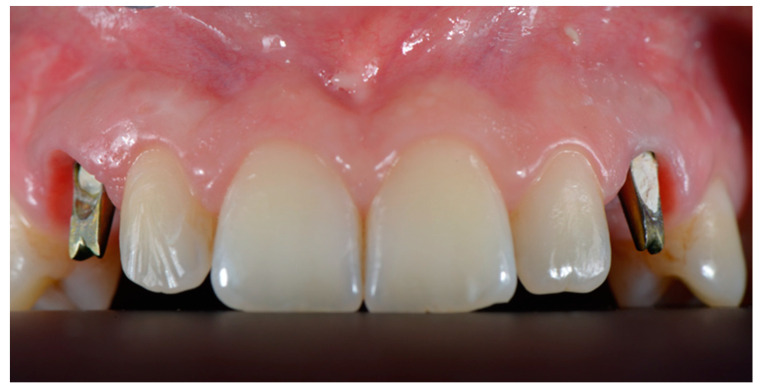

Final check before producing the zirconia element was performed positioning the crown on the abutment. If no color or shape corrections were needed, definitive zirconia restoration was positioned and cemented (Temp Bond, Kerr, FL, USA) (Figure 7 and Figure 8).

Figure 7.

Definitive restorations after 2-year follow-up.